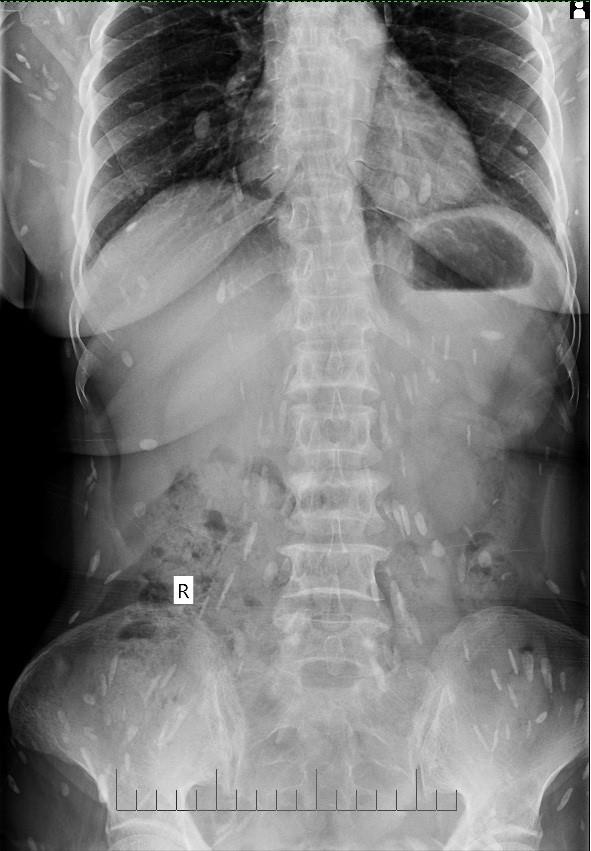

| Hình ảnh chụp X-quang tim phổi bệnh nhân Đ. Ảnh: Bệnh viện cung cấp. |

Qua thăm khám, xét nghiệm, siêu âm, chụp X-quang, các bác sĩ kết luận bệnh nhân bị mắc bệnh sán lá gan sinh sống trong cơ thể đã nhiều năm, đang sinh sôi, lan ra trong nhiều bộ phận cơ thể. Người bệnh được kê thuốc và hướng dẫn lên bệnh viện tuyến trên để theo dõi, điều trị tiếp.